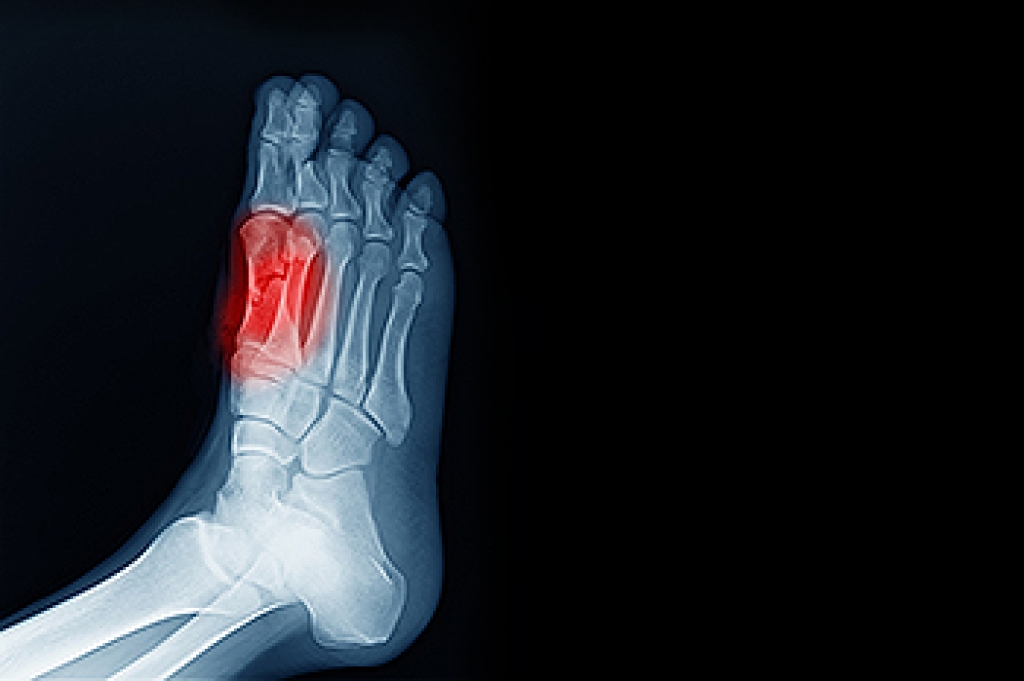

Be watchful for any pain or injury.

Have all injuries checked by a doctor as soon as possible.